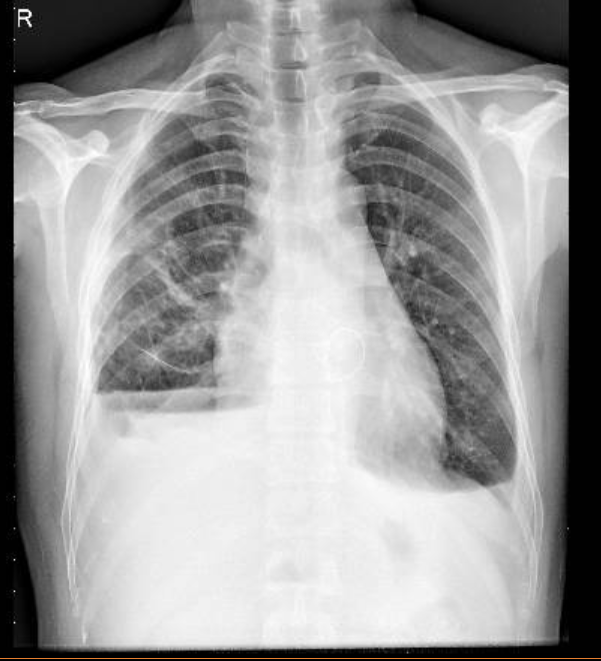

1-Xơ thâm nhiễm thùy giữa và thùy dưới phổi (P) 2-Tràn dịch màng phổi (T) 3-Tràn dịch màng phổi + tràn khí thành ngực hai bên